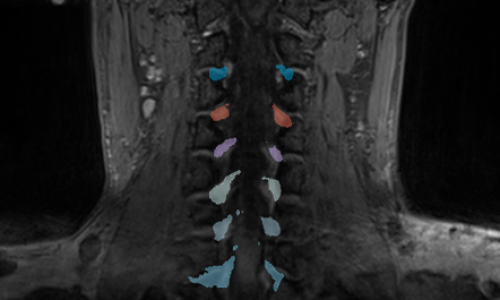

Explore highlights from PHRT’s work—showcasing cutting-edge research, innovative technologies, and collaborations that contributed to advancing individualized medicine.